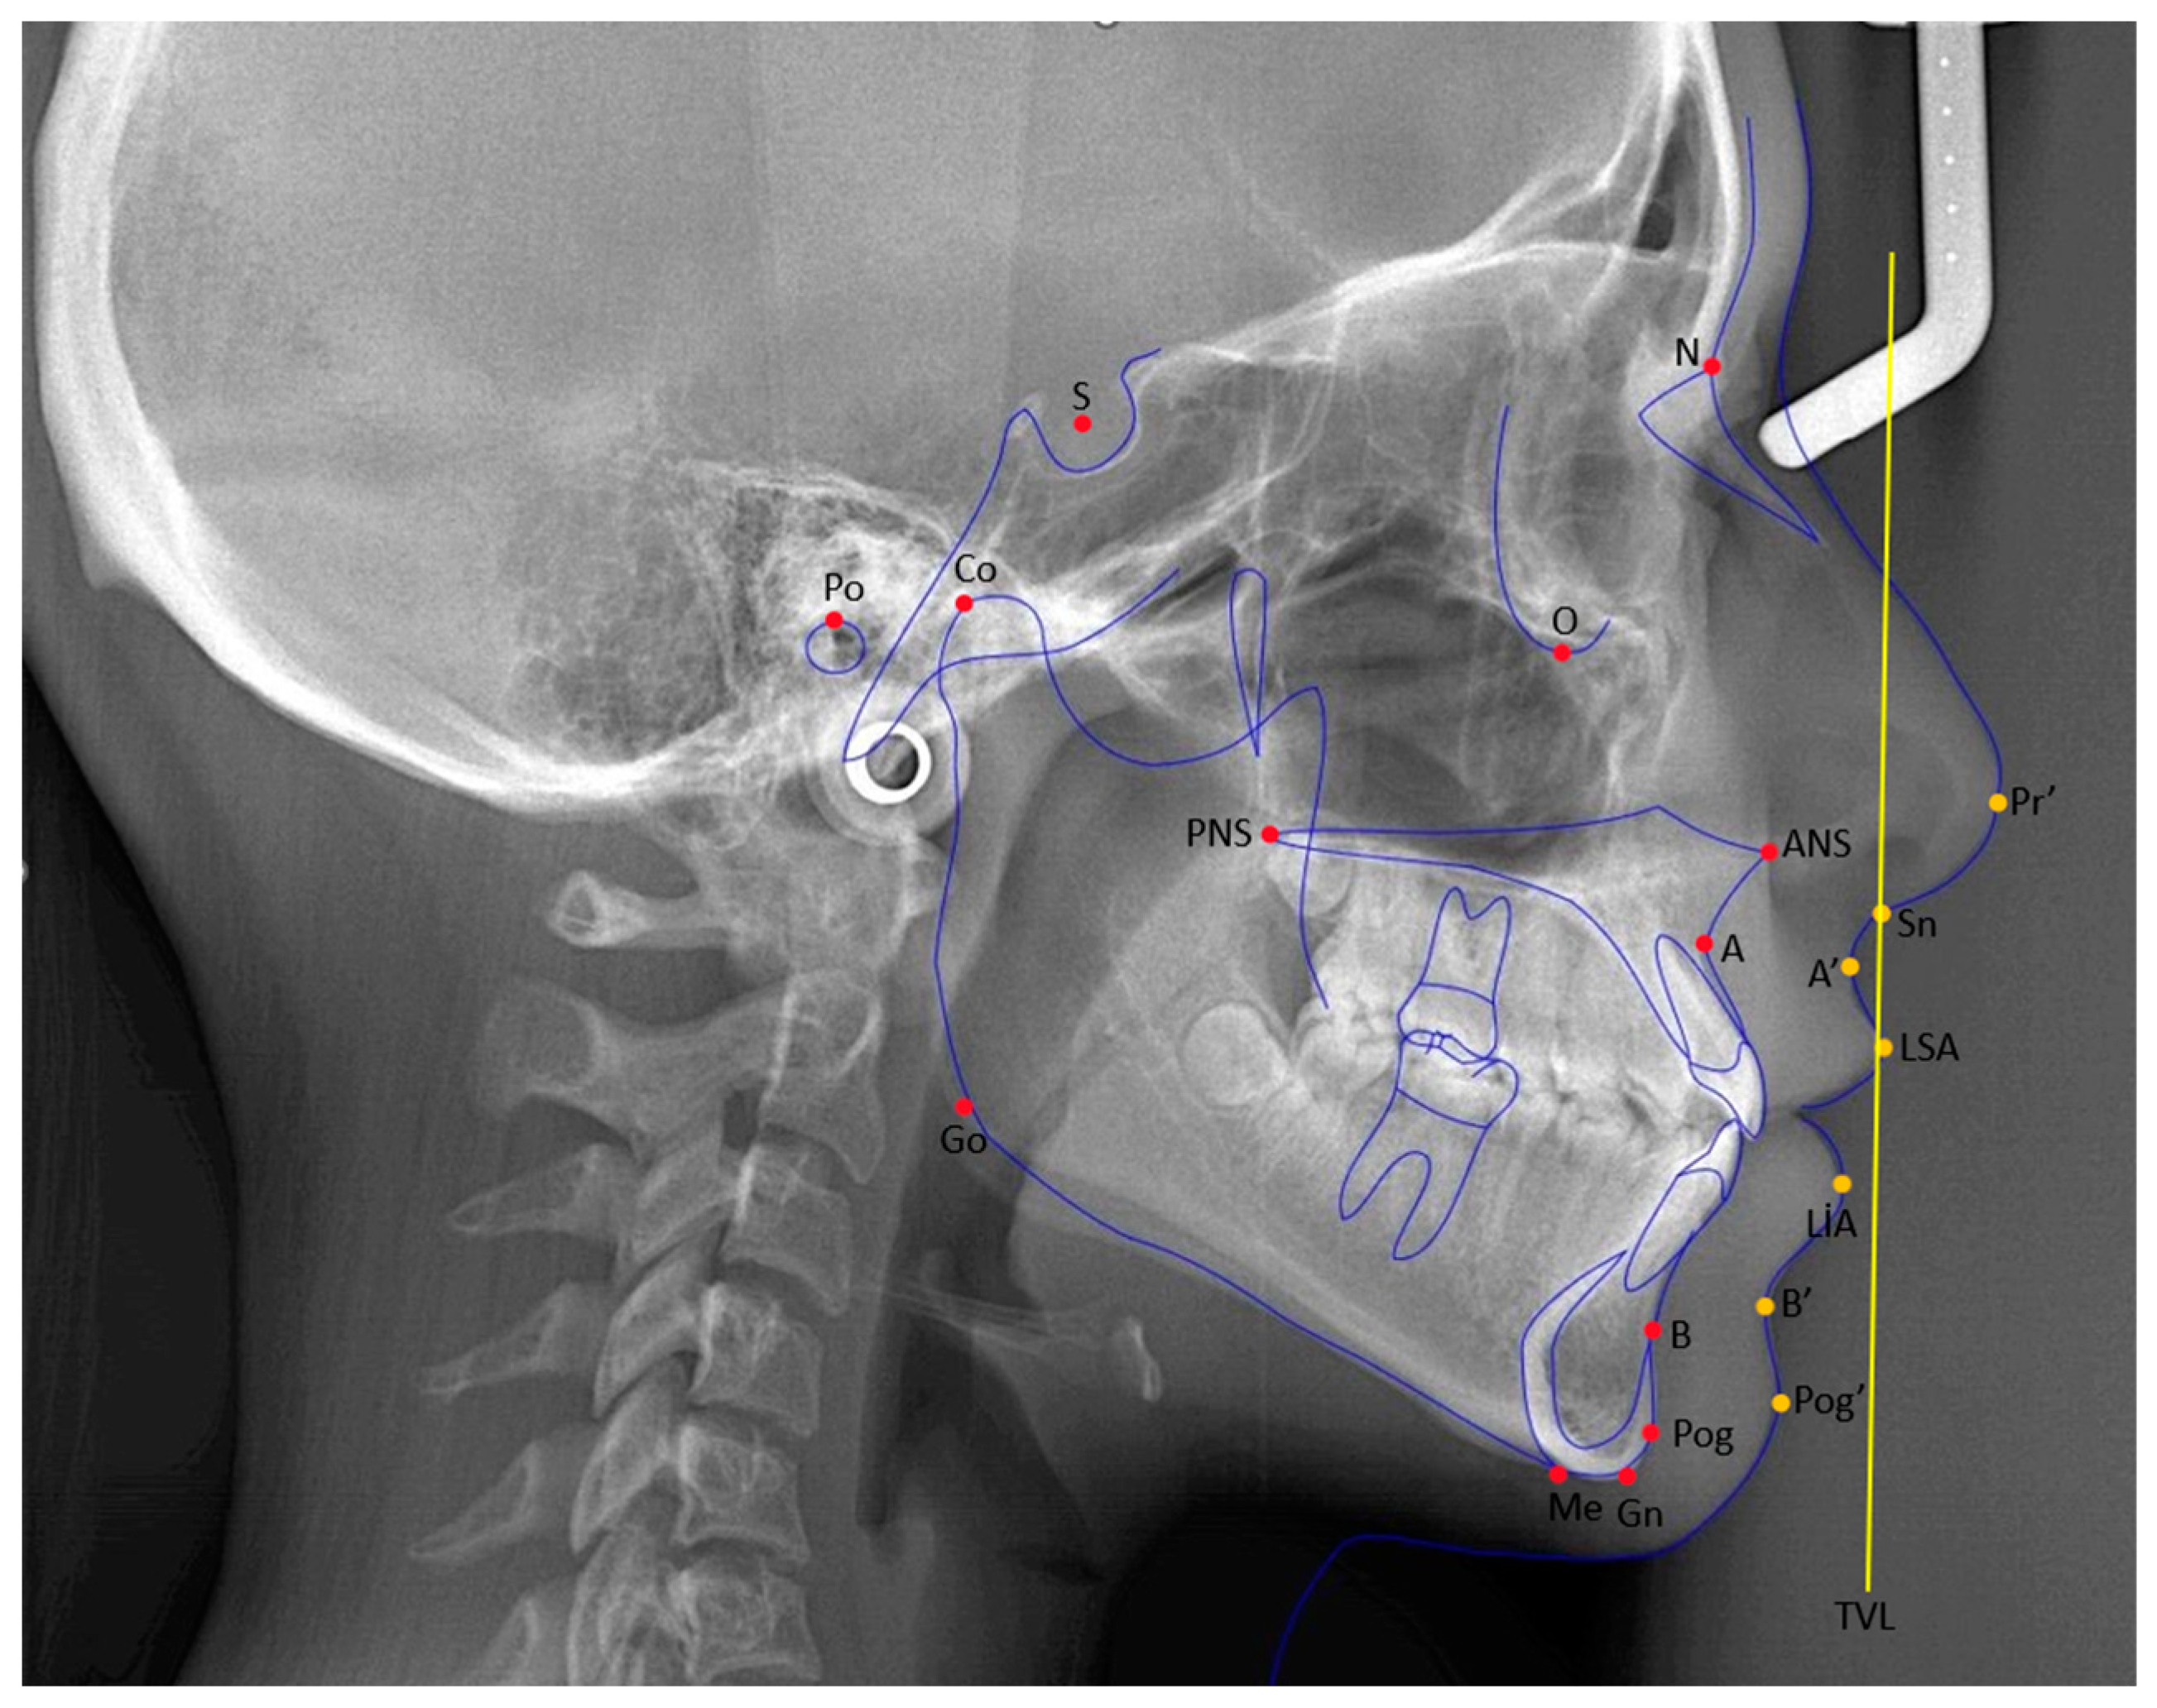

| Cephalometric Points | Definitions |

|---|---|

| Sella (S) | The geometric center of the sella turcica. |

| Nasion (N) | The most anterior and deepest point of the frontonasal suture. |

| A point (A) | The deepest point of the bony concavity on the anterior surface of the maxilla. |

| B point (B) | The deepest point of the bony concavity on the anterior surface of the mandible. |

| Porion (Po) | The uppermost point of the bony concavity that forms the external auditory canal. |

| Pogonion (Pog) | The most anterior point of the mandible in the sagittal plane. |

| Gnathion (Gn) | The most anterior and inferior point of the mandible. |

| Menton (Me) | The point where the lower border of the mandible meets the symphysis in the sagittal plane. |

| Gonion (Go) | The point where the bisector of the angle formed by the intersection of lines, drawn along the ramus and corpus of the mandible, cuts the ramus. |

| Maxillary incisor edge point | The point of the incisal edge of the most anteriorly positioned maxillary incisor. |

| Mandibular incisor edge point | The point of the incisal edge of the most anteriorly positioned mandibular incisor. |

| Subnasale (Sn) | The point of junction between the lower border of the nasal septum and the upper lip. |

| Labialis superior anterior (LSA) | The most anterior point of the upper lip in the sagittal plane. |

| Labialis inferior anterior (LIA) | The most anterior point of the lower lip in the sagittal plane. |

| Condylion (Co) | The most superoposterior point of the condyle in the sagittal plane. |